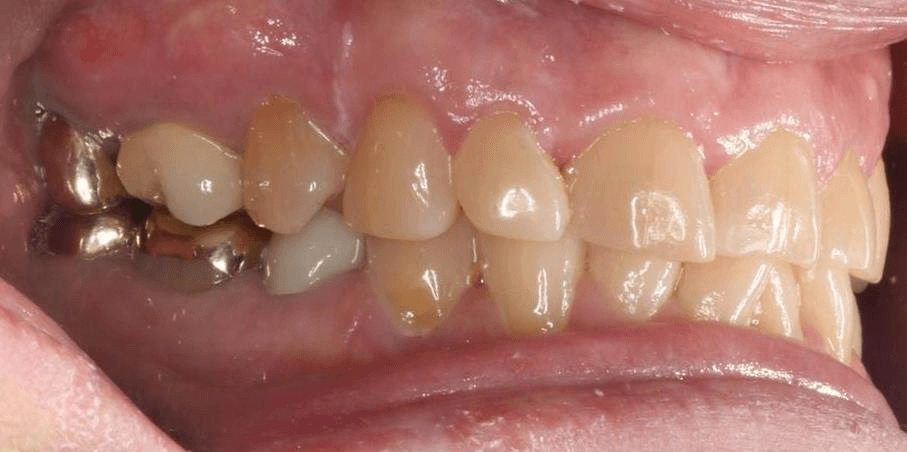

INTRAORAL